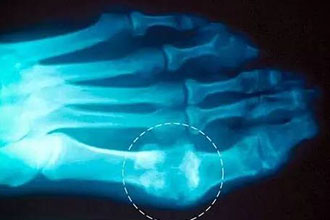

痛风是吃出来的?患者应避免突然受冷、剧烈运动科普中国-乐享健康 2018-11-29 作者:曾小峰 |